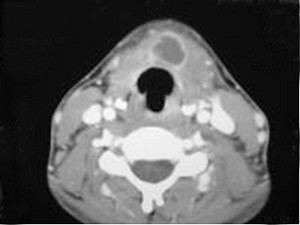

6.CT檢查結果見下圖,本患者應考慮為  (    )

正確答案:6.C;7.E